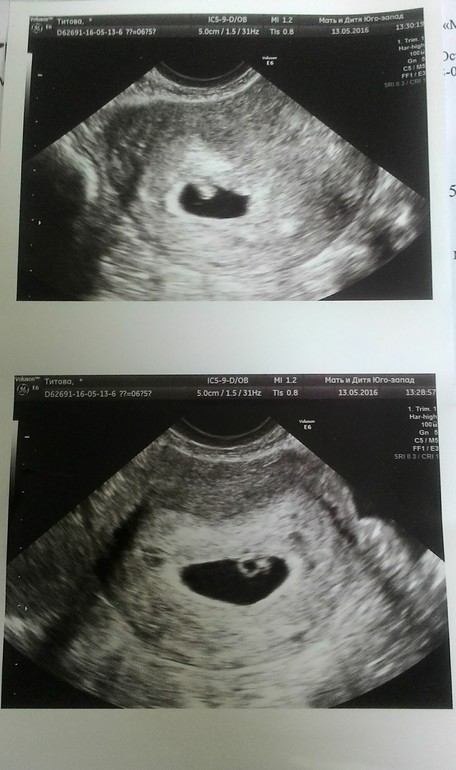

13.05. 2016 осмотр, СБ+, КТР-5мм(6 недель)

и точка растет))))

смотрела, и ревела, точнее слезы сами катились, как дурочка вобщем)))